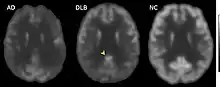

| FDG-PET of horizontal cross section brain. Brighter areas indicate higher metabolism, and the cingulate island sign is present in DLB (arrow), unlike Alzheimer's disease (AD) and normal (NC). | |

In medicine, the cingulate island sign is a finding on FDG-PET brain scans that metabolism in the posterior cingulate cortex is preserved. It can help to identify dementia with Lewy bodies (DLB) and distinguish it from Alzheimer's disease and other dementias.[1][2]